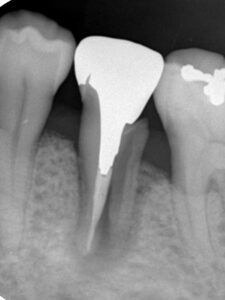

- X線で「J型」や「ハロー型」の骨吸収像

全体でなく、その歯だけ急に深い場合は要注意。 - 画像診断の活用

デンタルX線やCBCT(3D画像)で、骨の吸収形態を確認。

J型やハロー型の吸収なら、VRFの可能性が高いです。 - 咬合や力のかかり方を評価